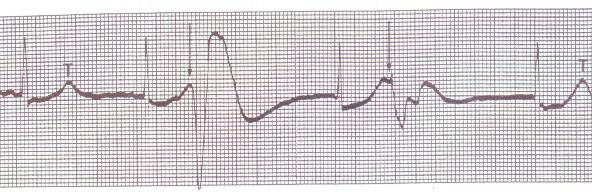

R - on T PVCs

4. Bigeminy PVCs (every other beat is a PVC)

Bigeminy PVCs (every other beat is a PVC)